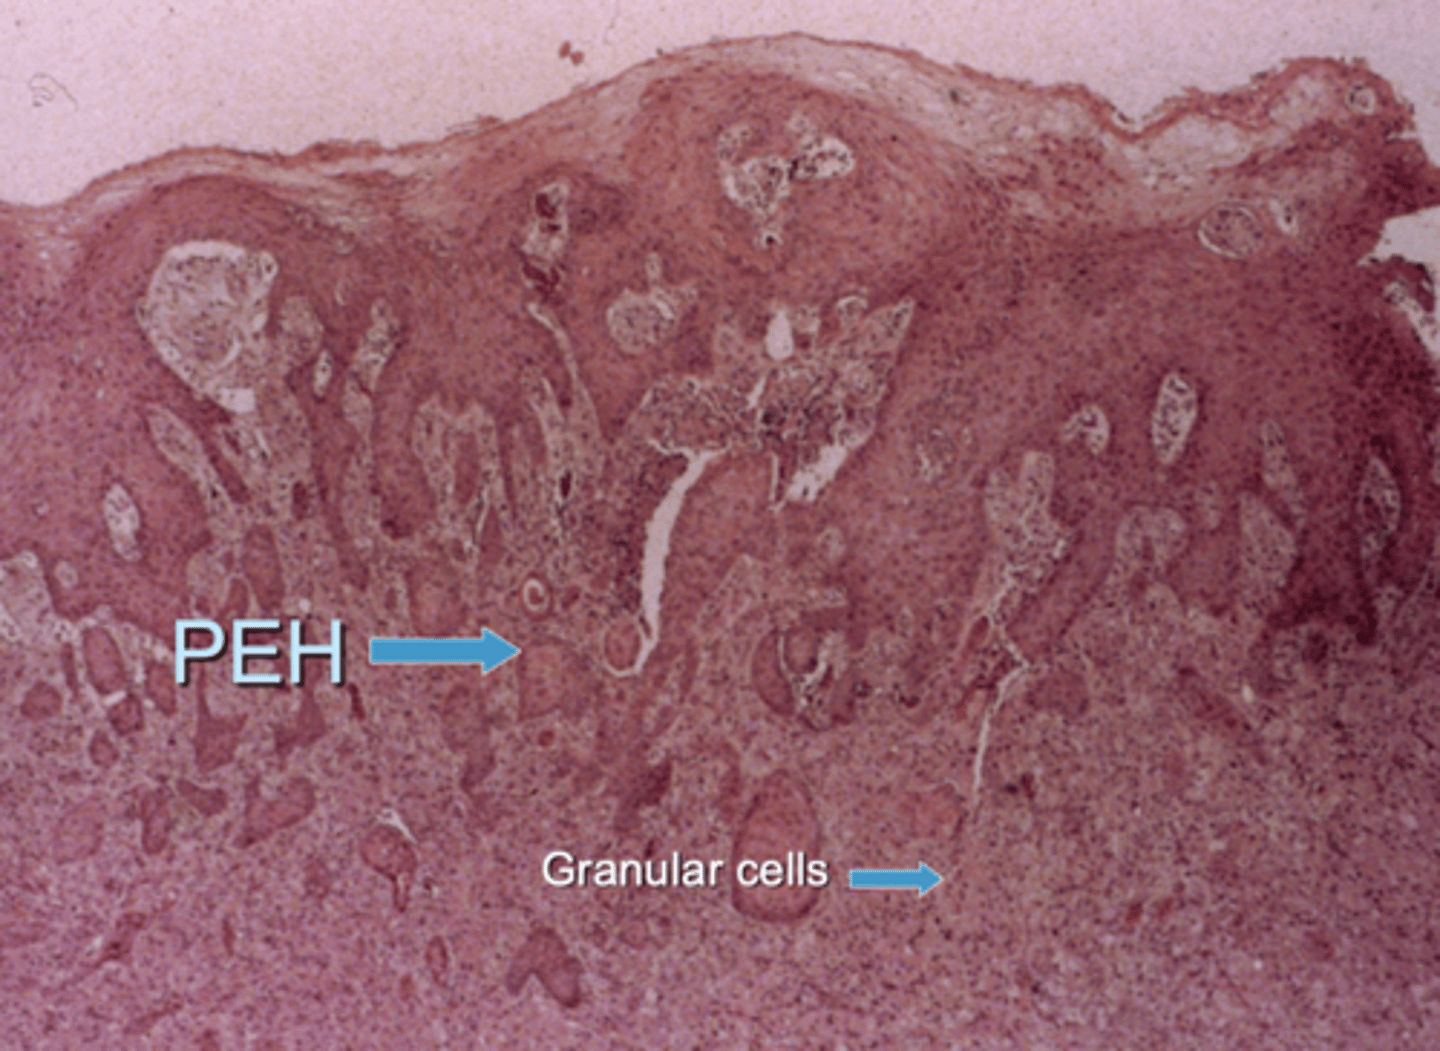

what is the most distinctive microscopic feature of a granular cell tumor?

pseudoepitheliomatous hyperplasia (PEH)

this can be mistaken for squamous cell carcinoma

what is the treatment for a granular cell tumor?

excisional biopsy - you can cut at the deep margin and they will still not recur

T/F: pseudoepitheliomatous hyperplasia (PEH) is found in congenital epulis

false

it is found in a granular cell tumor